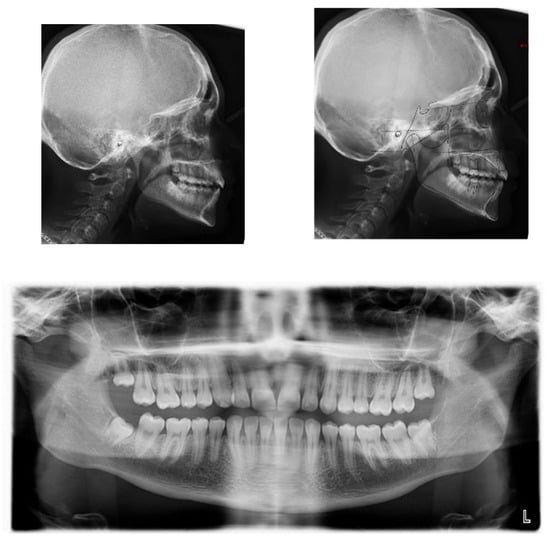

Figure 1.

A 17-year-old female with dentoskeletal Class I with an impacted upper right canine before treatment.

Intraorally, the patient had Class I molar and canine relation on both sides, along with normal overbite, overjet, and the retention of the deciduous canine.

The cephalometric analysis showed a skeletal Class I (ANPg +1.7°) with a good proportion of the maxillaries (SNA 84°; SNB 82.3°) in a normo-divergent vertical pattern (SN^Go-Gn = 32.8°) and a good inclination of the upper and lower teeth, respectively (I/ANS-PNS 116.2°; i/GoGn 91.6°) (Table 1).